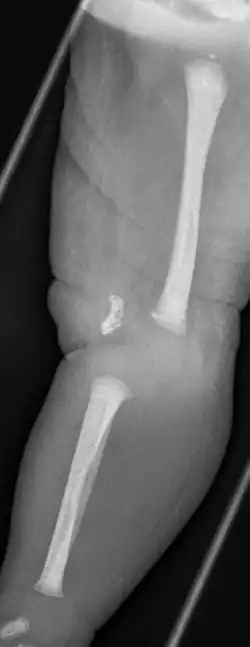

Die angeborene Knieluxation oder angeborene Kniegelenkluxation ist eine angeborene Luxations-Fehlstellung der Tibia zum Femur mit Überstreckung im Kniegelenk. Hinzu kommen eine Verkürzung der Oberschenkelstreckmuskulatur sowie häufig Dreh-, Valgusfehlstellungen und Fehlen der Kreuzbänder und Verlagerung der Kniescheibe nach außen.

Ein Röntgenbild kann zusätzliche knöcherne Veränderungen dokumentieren, eine Ultraschall-Untersuchung auch die Stellung der noch nicht verknöcherten Patella anzeigen. Die differentialdiagnostische Abgrenzung zum Genu recurvatum (mit regelrecht aufeinander stehenden Gelenkflächen) kann sonographisch, der Nachweis der Kreuzbänder – sofern für die Behandlung erforderlich – kann mittels MRT oder auch sonographisch erfolgen.[6]